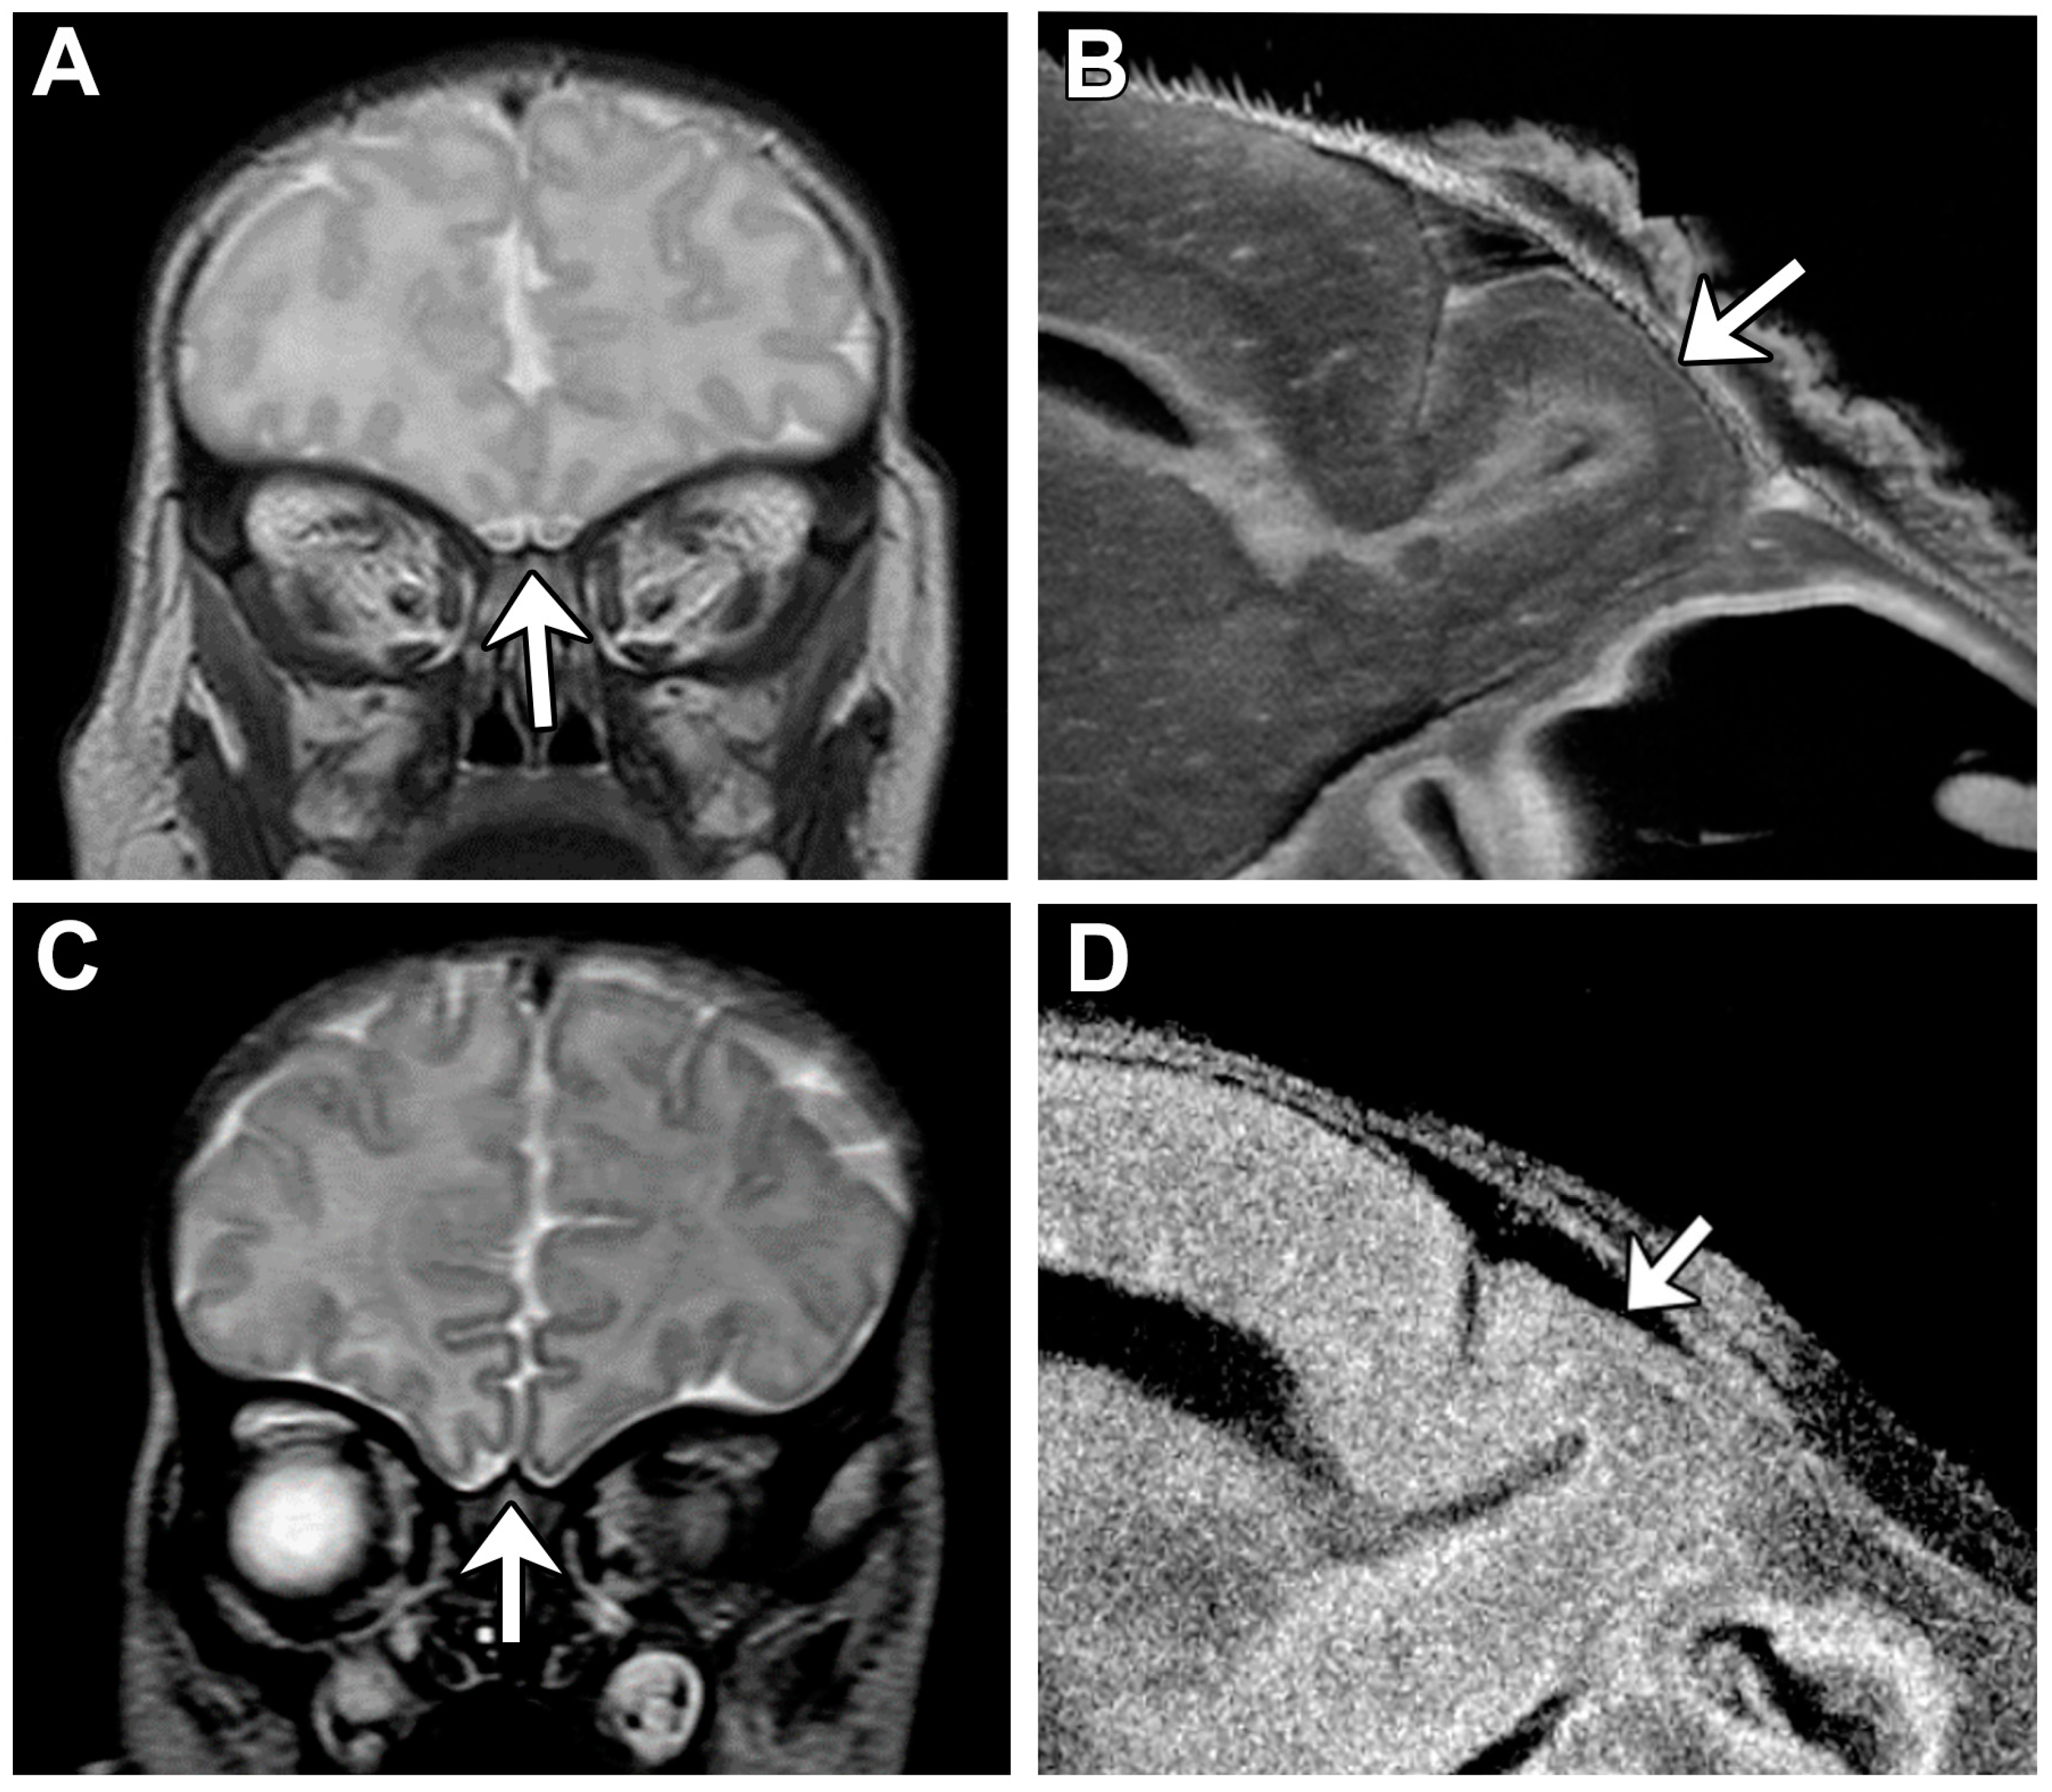

Lack of oral feeding before neonatal hospital discharge was associated with multiple morphological abnormalities of the components of the BDS including cerebellar hemispheres and vermis, hippocampus, bilateral olfactory bulbs and olfactory sulci, corpus callosum, increased supratentorial extra-axial fluid, as well as total increased BDS (Table 7). Hospital length of stay was associated with dysplasia of the cerebellar hemispheres and vermis, hippocampus, choroid plexus, brainstem, increased supratentorial axial fluid, and BDS (Table 7). A diagnosis of dysphasia was associated with dysplasia of the brain stem ((p = 0.001) Table 7). Gastrointestinal dysmotility, aspiration, gastroesophageal reflux, malrotation, and vocal cord paralysis demonstrated no significant associations with brain dysplasia (Table 7). Figure 2 panels A–D show some of the variations in hippocampal anatomy seen in the human population compared against that seen in the mouse in panels E and F. Figure 3 demonstrates olfactory bulb abnormalities in human infant CHD vs. control (A/C) and the mouse model (B/D). Figure 4 demonstrates cerebellar abnormalities in the human infant CHD vs. controls (A,B) and the mouse model (E,F).

Another important component of our paralimbic-related subcortical scoring system was the cerebellum. Cerebellar dysfunction has been linked with adverse neurodevelopmental outcomes [68,69,70]. Stoodley found that cerebellar damage or malformation present in early stages of development to be more detrimental than when obtained in adulthood and theorized that injuries could affect cerebral–cerebellar circuits that are crucial to development and learning [69]. Zwicker et al. found that preterm infants with exposure to morphine in the neonatal period had decreased cerebellar volumes and worse neurodevelopmental outcomes [70]. Additionally, our group has previously shown that CHD children with reduced cerebellar volumes scored worse in tests for working memory, inhibitory control, and mental flexibility [71]. We also demonstrated that the superior surface of the cerebellum, primarily composed of the posterior lobe and the midline vermis, is an area particularly susceptible to alterations in morphology, indicating possible regions specifically affected by dysmaturation in CHD [23]. Previous literature in combination with our BDS findings show the importance of the cerebellum toward neurodevelopment and suggest that insults or injury affecting proper cerebellar development may impact neurodevelopmental outcomes. Figure 4 demonstrates some of the commonalities seen between the mouse and human cerebellum; of note are the abnormal number of cerebellar fissures and small size.